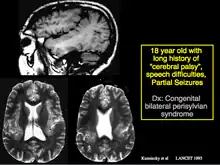

Kuzniecky described the Kuzniecky Syndrome in 1991, also known as perisylvian polymicrogyria.[6] The syndrome is characterized by seizures, cognitive abnormalities, and a peculiar inability to use the mouth and tongue muscles. This syndrome is recognized by as a specific malformation of the brain.[7]

MRI showing the abnormal infolding of the perisylvian region typical of this syndrome. The abnormality is due to polymicrogyria.